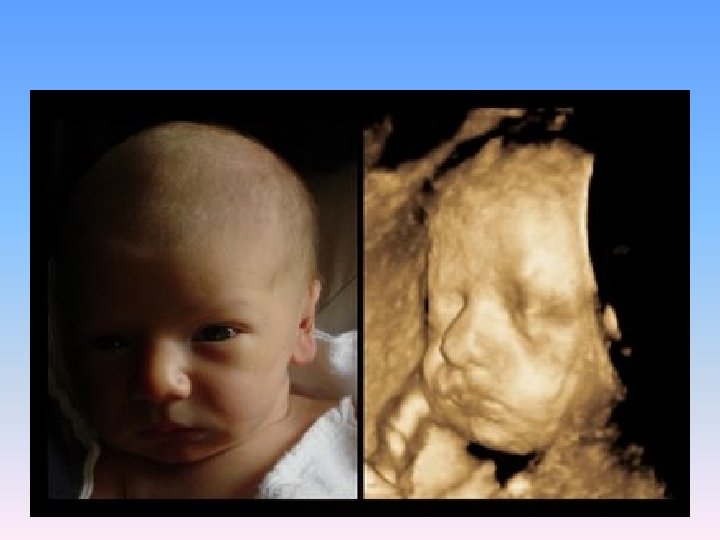

3 -D and 4 -D National Geographic Channel In The Womb